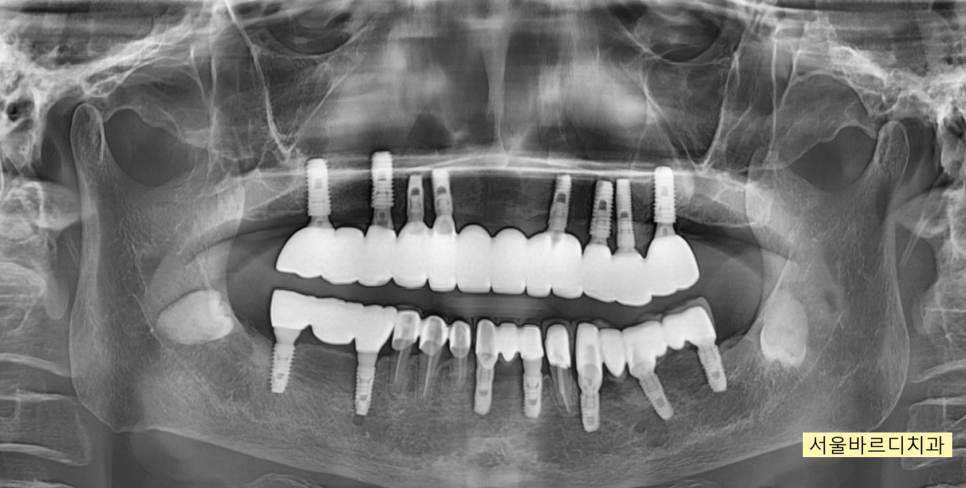

241031 치료계획입니다~~ 기존 심겨진 임플란트를 활용하면서 회복해주는 계획이죠.

241129

250210

수술은 네비게이션 임플란트 방식으로

한번에 진행되었고

250305

250324

치료 과정에서

기존에 심겨진 임플란트는 최대한 활용하였습니다.

임플란트는 뼈 안에 식립되어있고

높이를 올리는 것은 보철을 통해 해결해주기 때문에

문제가 되지 않습니다.

250314

치료가 끝난 모습입니다.

윗니가 아랫니를 덮는

정상적인 교합으로 마무리 되었습니다.